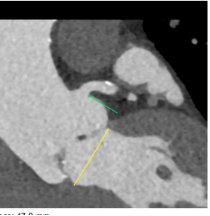

主动脉CT

原生物瓣形态:最大直径18.3mm;

冠脉风险尚可;冠脉切线面窦宽30mm,冠脉距离生物瓣距离>4mm,风险可控;

入路情况:升主有扩张,直径46mm,胸主腹主动脉无明显迂曲,双侧股动脉入路较好,右股可作为主入路;

考虑植入深度:生物瓣缝合环下5mm。